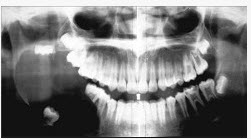

男,18岁,右颌下区反复肿胀半年,2天前再次发作,病程进展快,出现张口受限。X线片示右下颌角区沿颌骨长轴有单囊阴影,包绕右下颌第三磨牙牙冠。该病人最可能的诊断是()